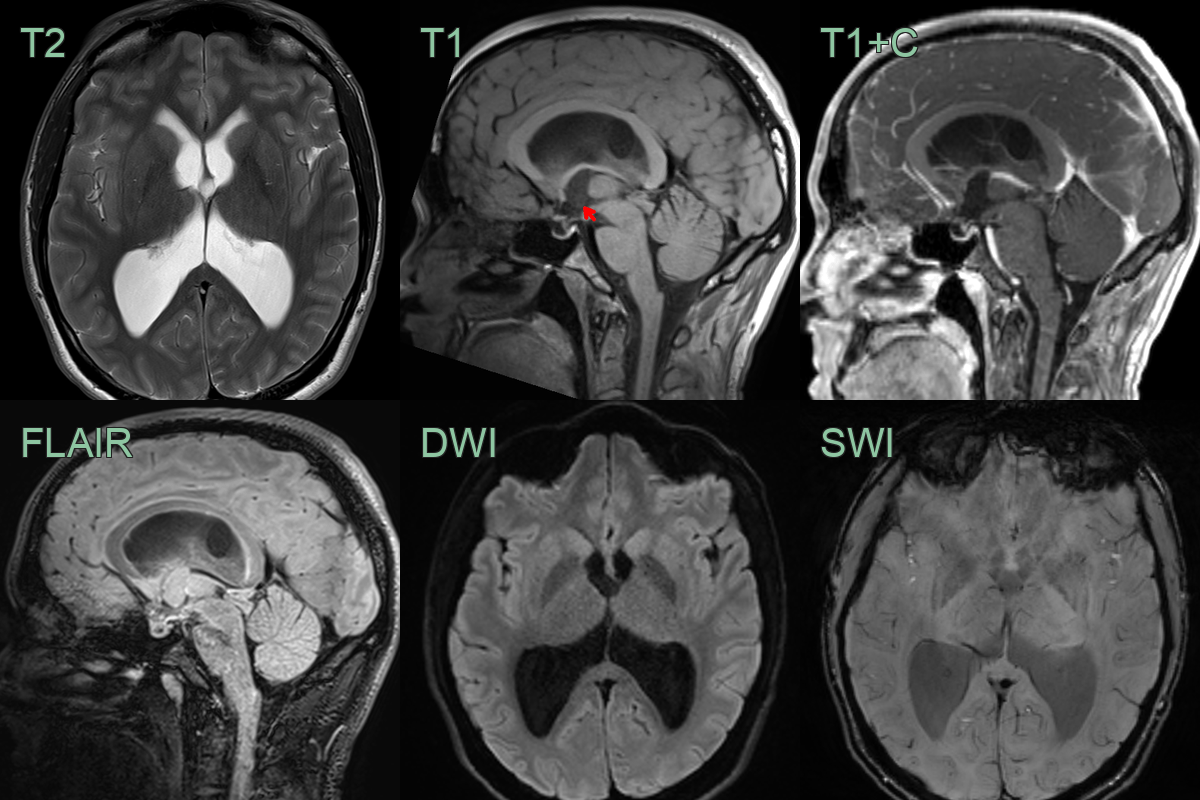

- MRI findings:

- T1-weighted: Variable signal intensity (hyperintense to CSF)

- T2-weighted: Usually hypointense to CSF

- FLAIR: Hyperintense signal

- Contrast enhancement: Typically minimal or absent

- DWI: No restricted diffusion